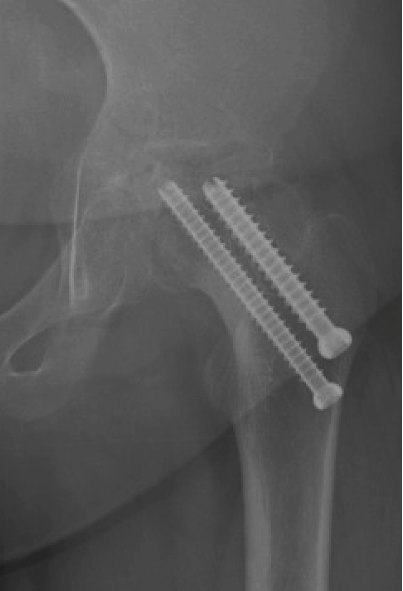

Fixation failure

Cam FAI